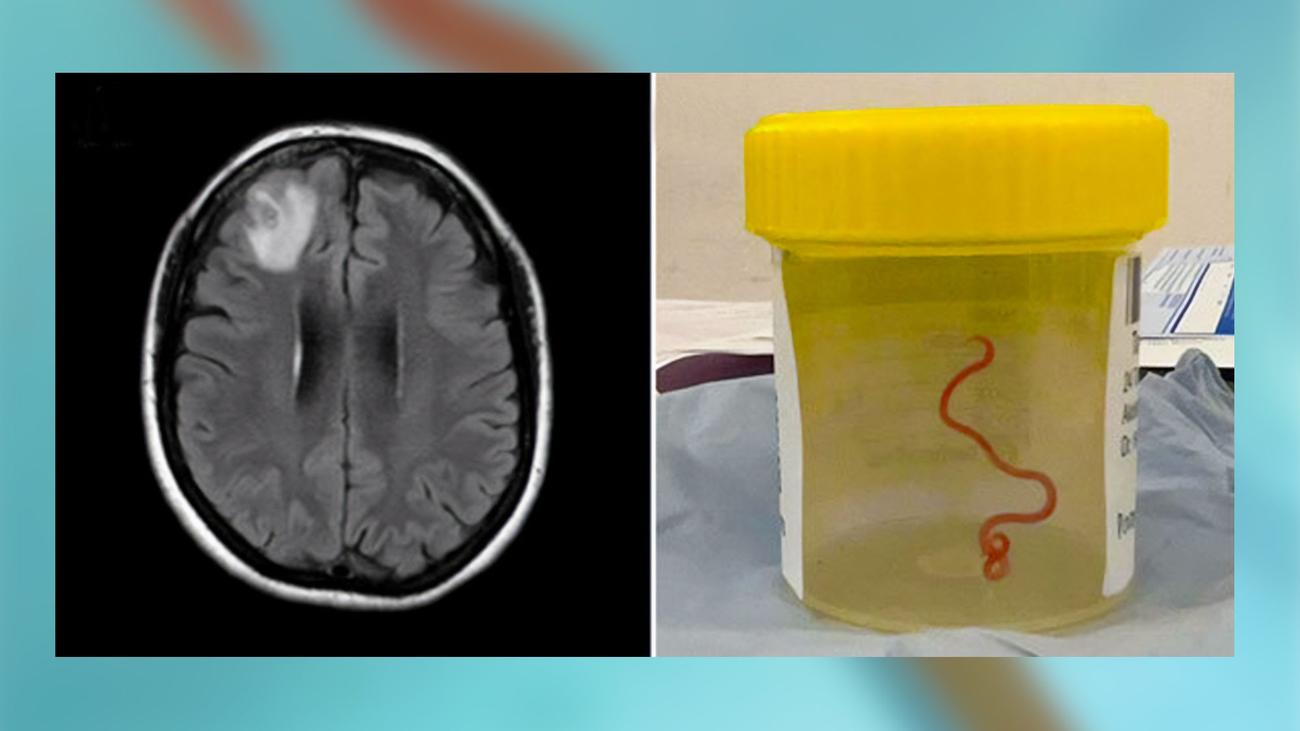

Παρασιτικό σκουλήκι βρέθηκε «ζωντανό και στριφογυρίζει» στον εγκέφαλο μιας γυναίκας

Νευροχειρουργός στην Αυστραλία

έβγαλε ένα ζωντανό σκουλήκι μήκους 3 ιντσών από τον εγκέφαλο

μιας 64χρονης γυναίκας τον Ιούνιο του

2022

. Το στρογγυλό σκουλήκι

Οφιδασκάρης ρομπέρτση

είναι εγγενές στην Αυστραλία και οι προνύμφες του ήταν επίσης παρούσες σε άλλα όργανα στο

σώμα

του ασθενούς, συμπεριλαμβανομένου του ήπατος και των πνευμόνων. Αυτή είναι η πρώτη γνωστή ανθρώπινη περίπτωση αυτής της παρασι

τι

κής μόλυνσης και περιγράφεται στο α

μελέτη περίπτωσης που δημοσιεύτηκε στο τεύχος Σεπτεμβρίου 2023 του περιοδικού

Αναδυόμενα Λοιμώδη Νοσήματα

.

μετά από τρεις εβδομάδες διάρροιας και κοιλιακού πόνου, ακολουθούμενα από ξηρό βήχα, νυχτερινές εφιδρώσεις και πυρετό. Τον Ιούνιο του 2022, αντιμετώπιζε επίσης λήθη και κατάθλιψη και παραπέμφθηκε στο νοσοκομείο της Καμπέρα. Ενώ ήταν εκεί, υποβλήθηκε σε εγχείρηση εγκεφάλου όταν μια μαγνητική τομογραφία αποκάλυψε κάποιες ανωμαλίες.

Η νευροχειρουργός Hari Priya Bandi εκτελούσε βιοψία όταν χρησιμοποίησε λαβίδα για να βγάλει το παράσιτο από τον εγκέφαλο της γυναίκας. Επικοινώνησε αμέσως με τον λοιμωξιολόγο Sanjaya Senanayake του νοσοκομείου της Καμπέρα, λέγοντας «Θεέ μου, δεν θα πιστεύεις αυτό που μόλις βρήκα στον εγκέφαλο αυτής της κυρίας — και είναι ζωντανός και στριφογυρίζει», είπε ο Bandi.

σύμφωνα με

Ο κηδεμόνας

.

Μια ζωντανή μορφή προνύμφης τρίτου σταδίου

Οφιδασκάρης ρομπέρτση

που είναι περίπου 3 ίντσες μήκος και μόνο ένα χιλιοστό σε διάμετρο. Το σκουλήκι φαίνεται κάτω από ένα στερεομικροσκόπιο.

ΠΙΣΤΩΣΗ: Hossain M/Kennedy KJ/Wilson HL.